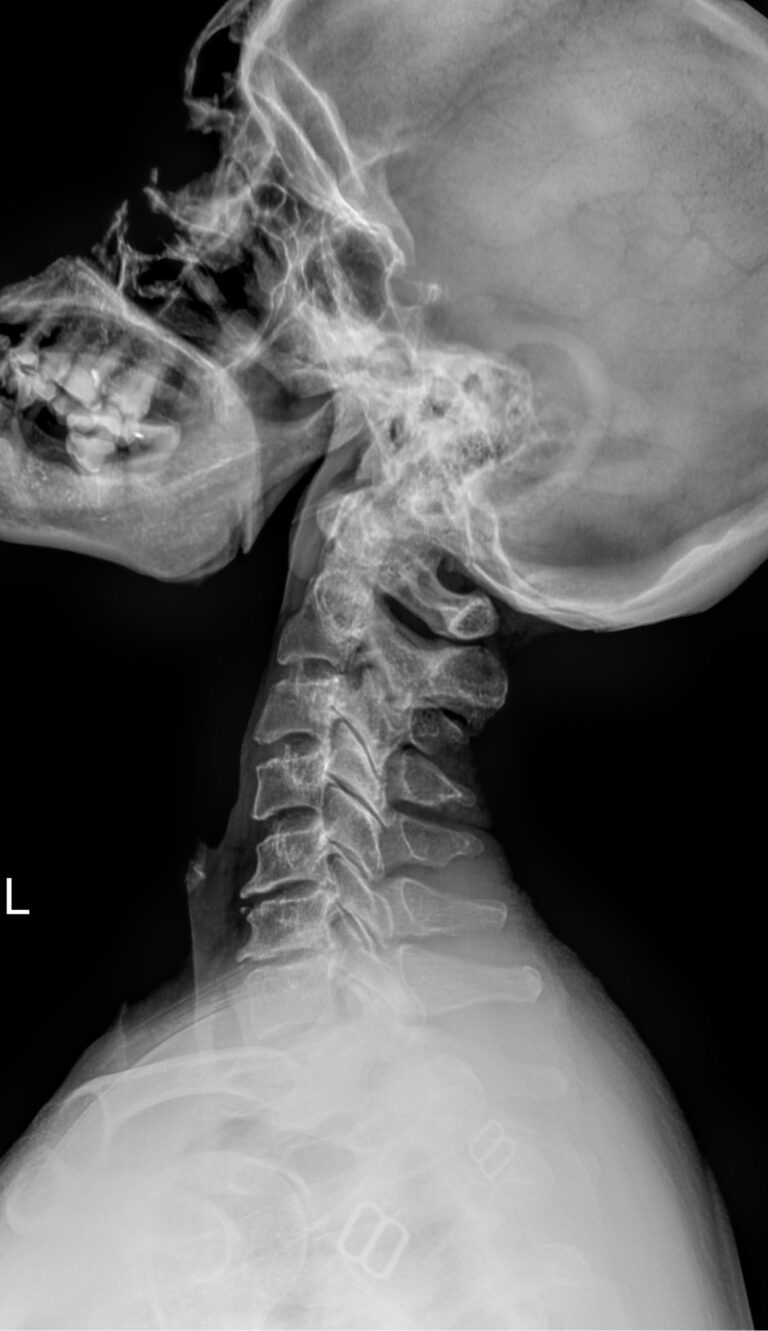

Как и другие кости, шейные позвонки отлично визуализируются с помощью рентгена. На снимках отчетливо видны признаки острых и хронических патологий, а часть врожденных аномалий обнаруживается случайно именно на рентгенограммах. В снимок попадают средние и нижние шейные, а также 2-3 верхних грудных позвонка. Для исследования двух верхних позвонков требуется специальная  проекция ― «через открытый рот».

Снимки могут быть назначены в 2 и более проекциях, которые указаны в направлении:

• Прямой ― лежа на спине с чуть запрокинутой головой;

• Боковой ― чаще стоя или сидя боком к пластине детектора;

• Косой ― тоже стоя или сидя, повернувшись к пластине на 30-45о.